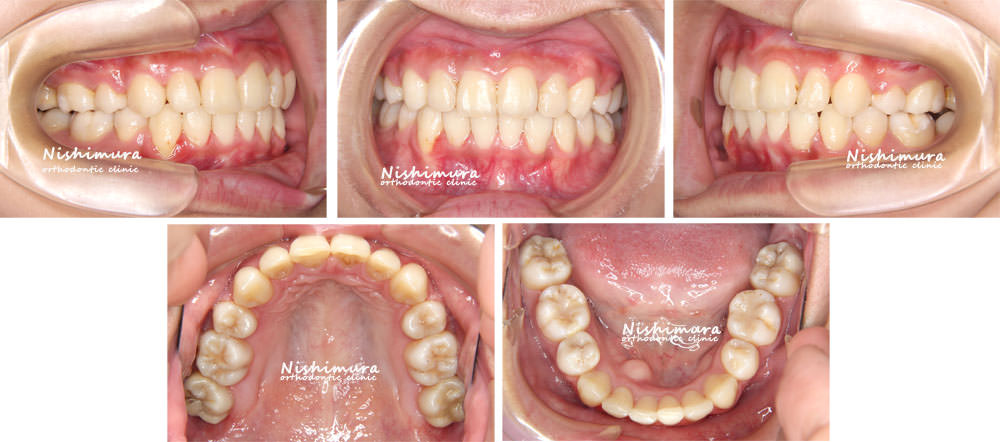

治療前

治療前の写真

治療後

治療後の写真